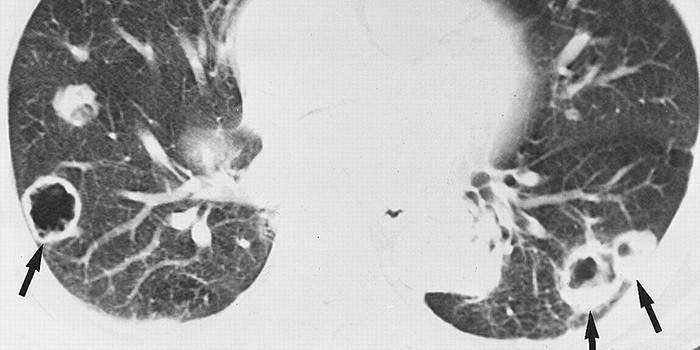

- Hematogeno. As metástases são transportadas junto com o sangue. Células se movem através dos vasos, entram em outros lugares, às vezes muito distantes da formação maligna primária. Freqüentemente, os órgãos que possuem uma ampla rede capilar tornam-se alvos, de modo que os pulmões e o fígado são mais freqüentemente afetados.

- Quando metástases cancerosas entram nos pulmões, ocorrem sintomas que indicam outros problemas. Este órgão deve ser verificado se uma pessoa se queixar de dor no peito, falta de ar, tosse (com sangue, seco, molhado).

- Pulmões. Com uma única ou múltipla metástase desse órgão, sua aparência torna-se um fator desfavorável antes de 12 meses após a cirurgia para remover o local primário do câncer. Sobrevivência por 5 anos após uma única neoplasia secundária, o tratamento adequado é de cerca de 40%.